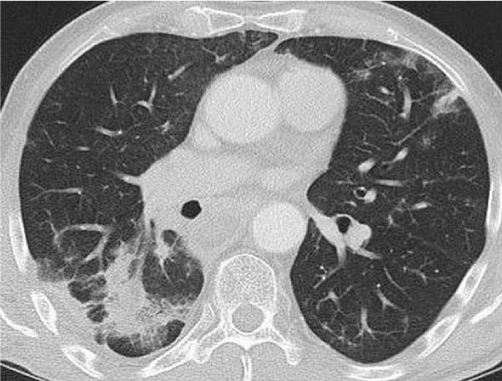

Diagnostic imaging was performed including a Computed Tomography (CT), a cine esophagography and a Fluorodeoxyglucose (FDG) Positron Emission Tomography (PET). The multi-slice CT of the chest and abdomen was performed in 2 x 64 x 0, 6 mm Collimation (Siemens Somatom Definition AS +), with oral and i. V contrast medium application. CT scan revealed a polylobulated mass (tumour size of 330x85x65 mm) of the esophagus with fatty and soft tissue density, extending from the thoracic inlet to the distal esophagus and causing a tracheal compression as well as a compression of the right main stem bronchus (Figure 3). There were no metastatic lesions detected in the CT. In the PET only the tumour masses in the middle part of the mediastinum showed a FDG uptake with a maximal Standard Uptake Value (SUV) of 7,4 (Figure 4).

Figure 3: Computed tomography scan of the chest: large tumour mass with multiple circumscribed lobulations with fat and soft tissue density extending from the thoracic inlet to the lower mediastinum.

A follow up one year after tumour debulking and 10 months after the radiation therapy showed a significant decrease of the tumour mass continuing to spread from the cricopharyngeal area down to the carina, but the transversal extent was reduced (from about 70 x 50 x 110 mm to 59 x 56 x 90 mm (width x depth x length ). In addition, new bipulmonal infiltrates compatible with postradiogenic changes due to fibrosis appeared, mostly localized in the right lower lobe (Figure 11). No metastatic lesions were detected. The last follow-up after 4 years displayed a stable disease in CT-scans (data not shown).